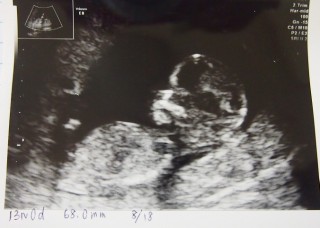

本当は13週5日に受診する予定でしたが突然出血した為、急遽病院へ。 心臓も元気に動いてて一安心(*´ー`) 9週5日から4週間ぶりでしたが、おっきくなってて嬉しいです!

CRL68mm 18日間で37mmも大きくなってました!染色体異常のエコー検査も受けましたが異常なしでした。